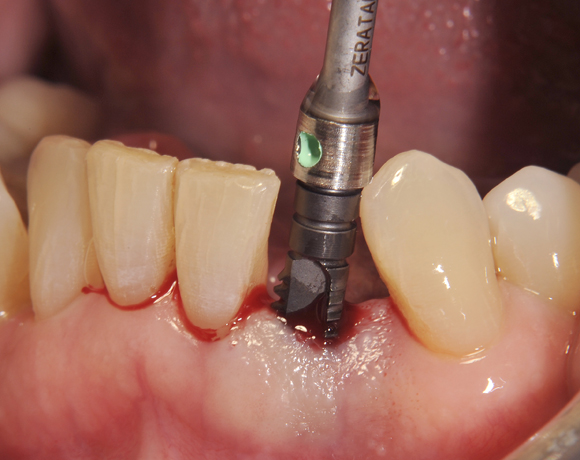

Am Beispiel dieses Patientenfalls wird gezeigt wie ein Einzelimplantat für den Unterkieferfrontzahn 33 eingesetzt wird.